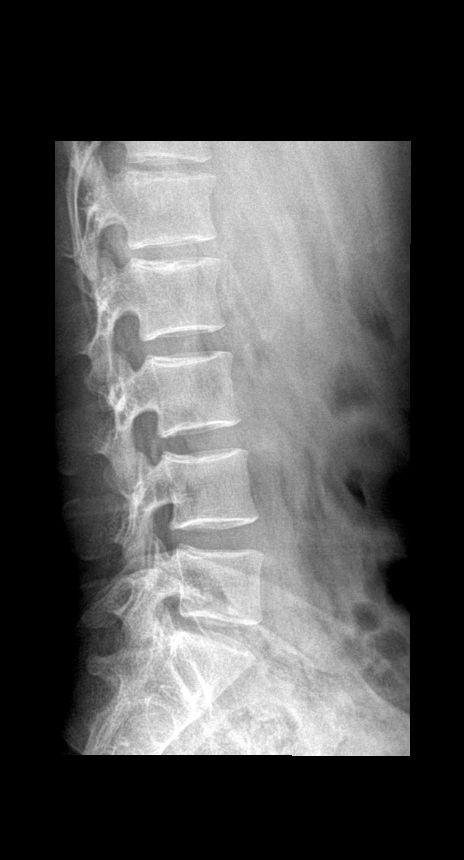

男 19岁 外伤 平对脐平面按压疼痛